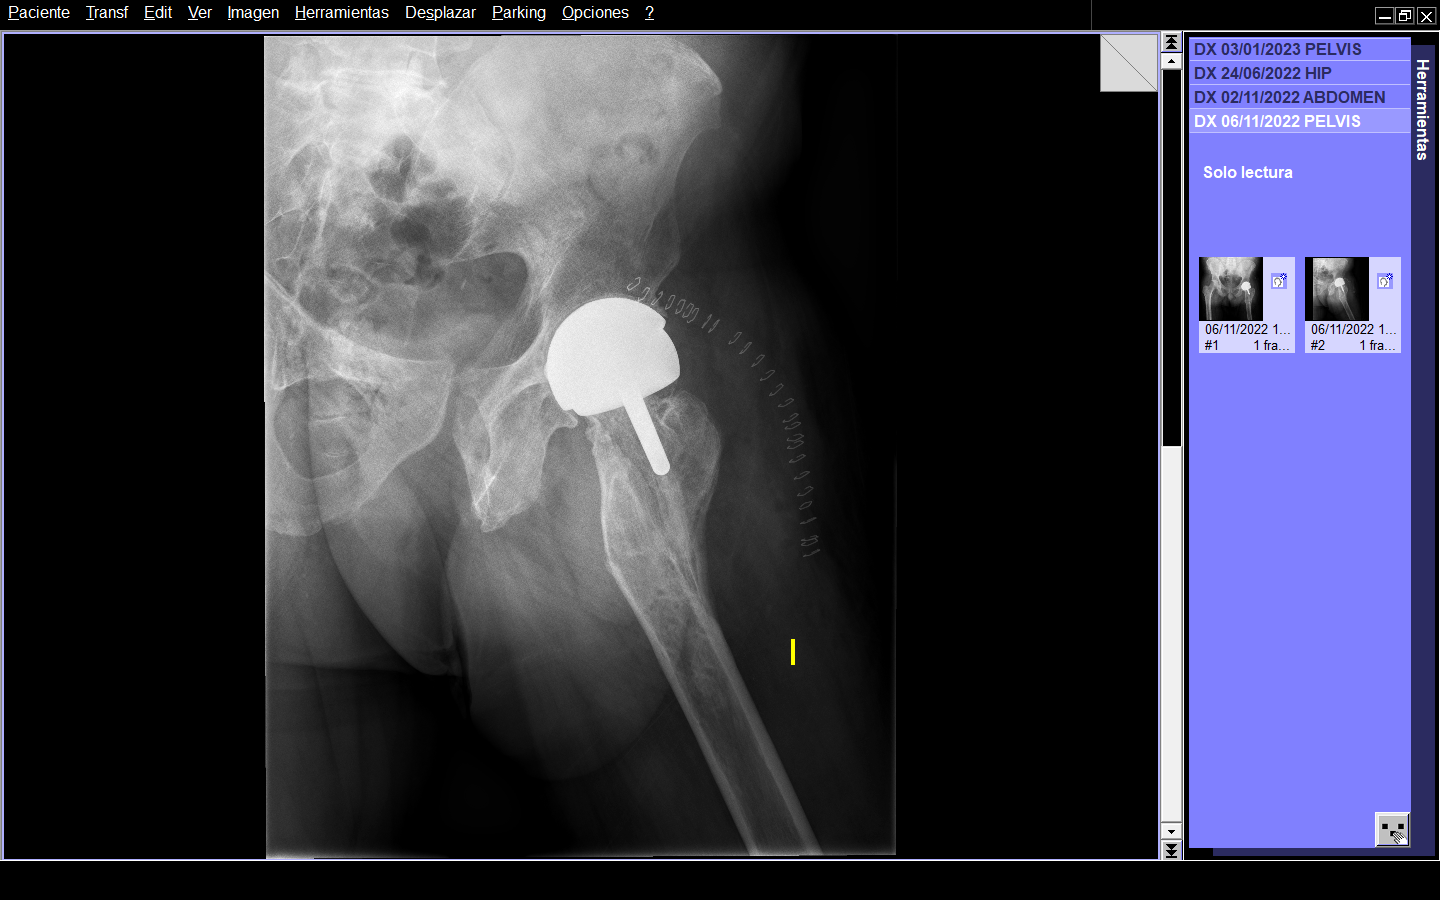

Radiográficamente, en AP presentaba deformidad en fémur proximal izquierdo de 160º en valgo, disminución del espacio articular, geodas en cabeza femoral. En la radiografía lateral se observaba curvatura en la metáfisis femoral con ápex posterior de 27º. (Figura 1 y 2)

Figura 1. Radiografía AP de ambas caderas.

Figura 2. Radiografía axial de cadera.